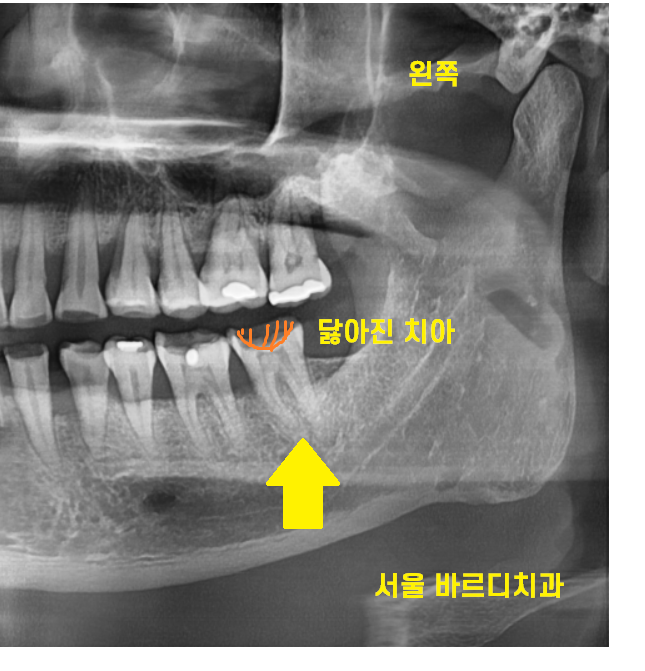

23.10.10

환자분께서는 신경치료 후 보철을 원하지 않으셨습니다.

그래서 신경치료를 위해 뚫어둔

구멍만을 메꿔서 치료를 마무리 해드렸습니다

환자분께는

신경치료 후 보철을 하지 않으면 발생할

문제점에 대하여 충분히 설명을 드렸습니다.

환자분 , 보철을 해주는 것은 치아를 보호하기 위해서입니다.

단단한 힘을 받게되면

치아가 금이가거나 부러질 수 있어요.

단단한 음식은 반드시 피해주세요!!

그리고 정확히 6개월뒤

환자분께서 망월동 치과를 다시 방문하셨습니다.

이가 갈라진것 같아요

23.10.16

네...

이가 반으로 갈라졌습니다.

이런 불상사를 방지하기 위하여

신경치료 후 보철을 해야한다고 말씀드리는거에요.